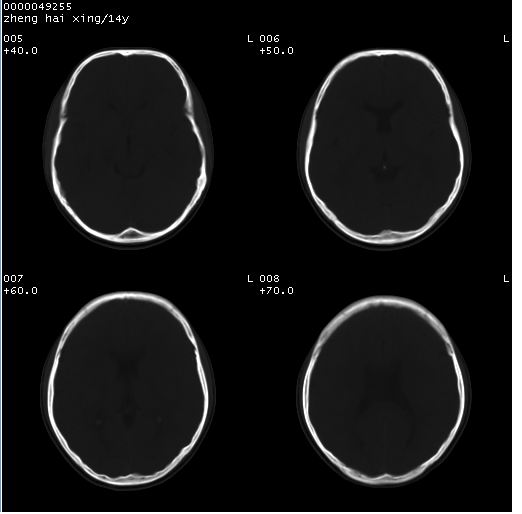

颅脑ct轴位平扫(层厚、层距均为10mm),图像如下:

调一下窗寛窗位,或者透明隔太薄,容积效应而显示不好。